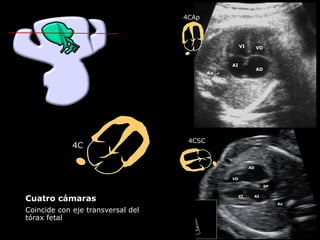

Cuatro cámaras

Coincide con eje transversal del

tórax fetal

4CSC

4CAp

4C